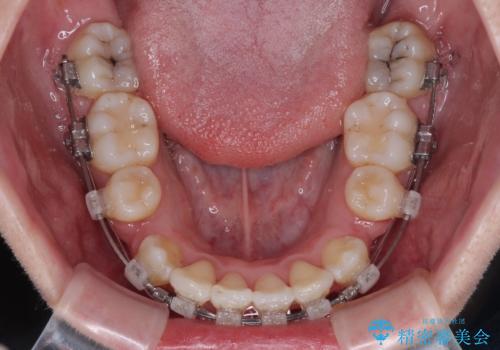

- クリアブラケット

口元を積極的に引っ込めるために、上下左右の小臼歯計4本を抜歯することとしました。

舌の突出癖が強いため、しっかりと口元を引っ込めるため、舌のトレーニングをしっかりと行いながら矯正治療を行うこととしました。